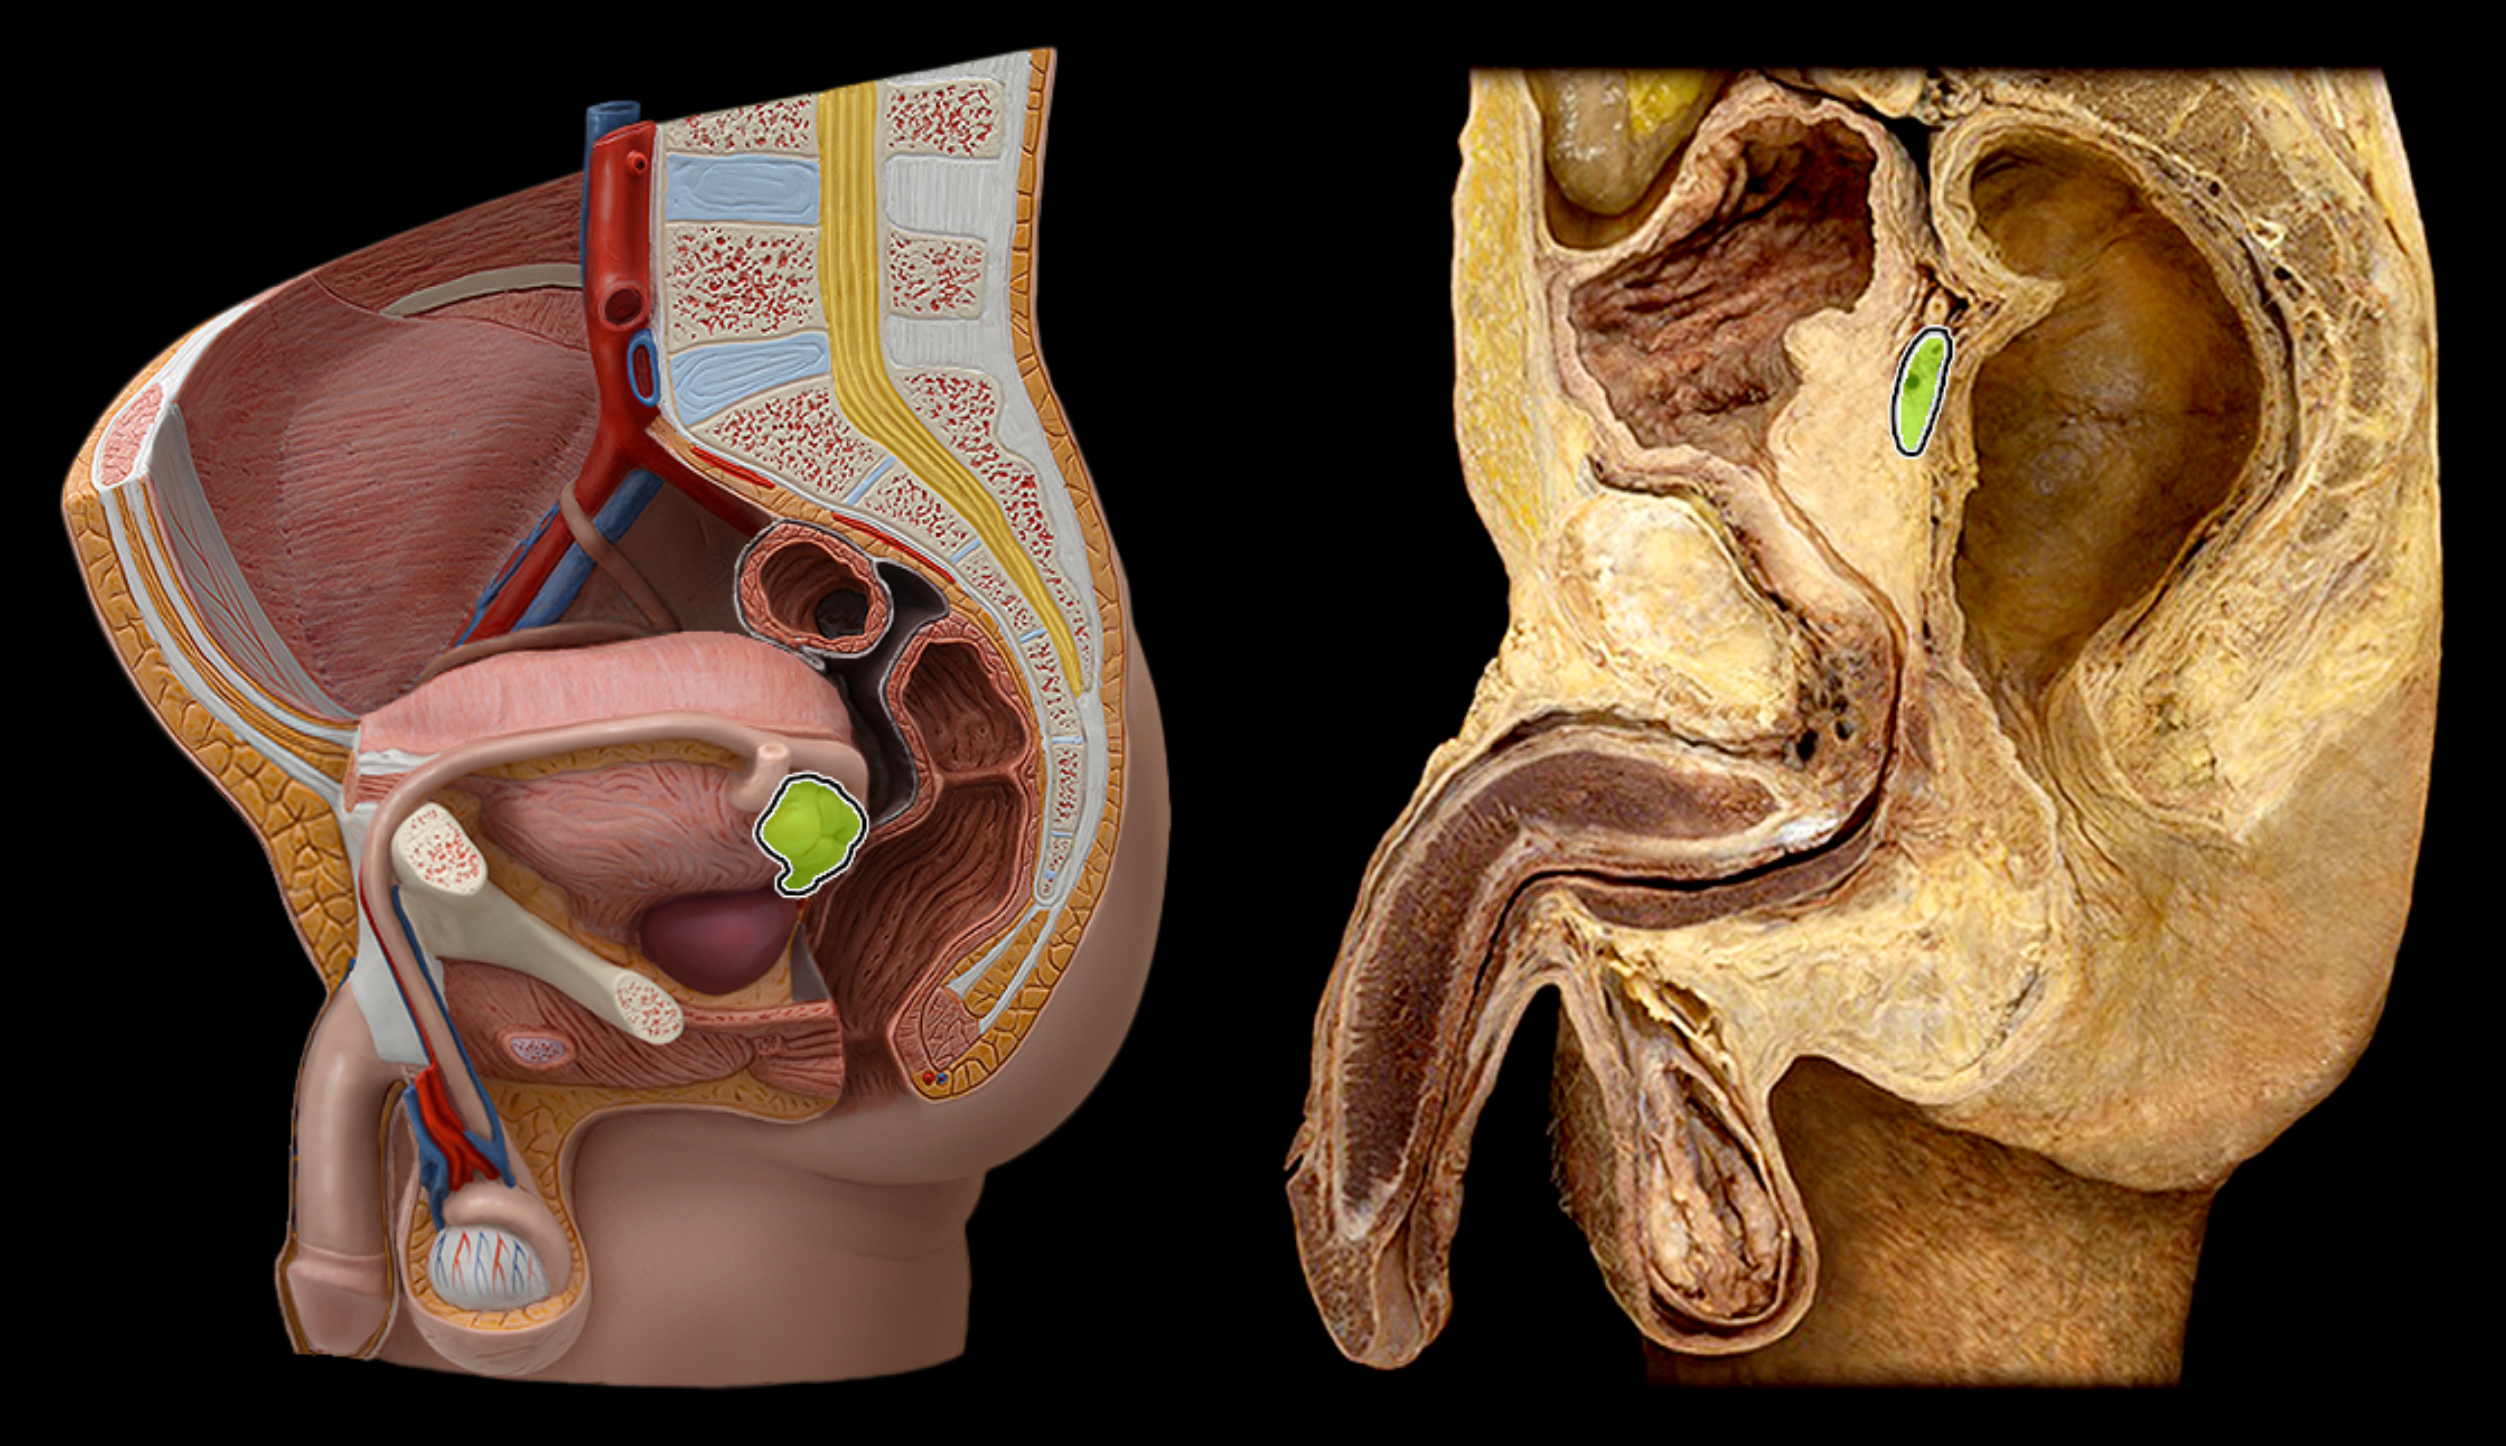

Vas deferens (ductus deferens)

Ejaculatory duct

Seminal vesicle

epididymis